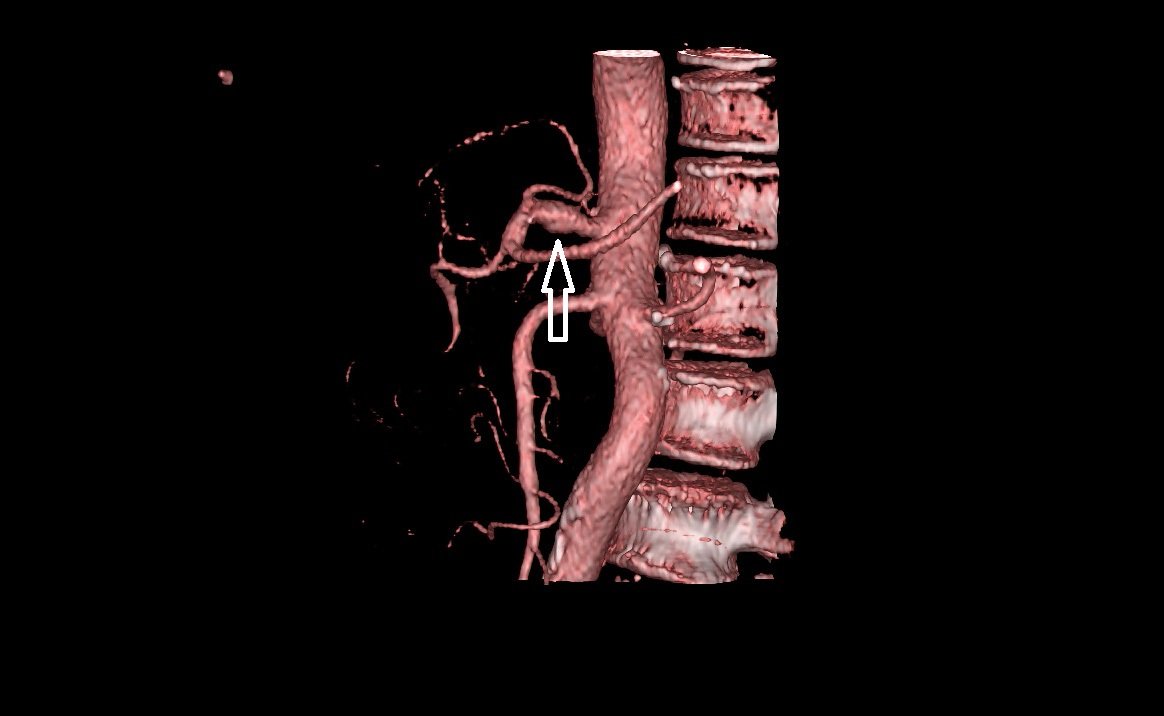

Trở lại với trường hợp của bệnh nhân P.H với nhiều bệnh lý phức tạp, các bác sĩ Khoa Tim mạch – Đột quỵ đã lên phác đồ điều trị phù hợp và an toàn nhất cho bệnh nhân. Bệnh nhân được kiểm soát chặt chẽ tình trạng huyết áp, nhịp tim, đường máu, mỡ máu, cân bằng dịch điện giải, sử dụng kháng ngưng tập tiểu cầu ngăn hình thành các cục máu đông cấp tại chỗ lóc tách, PPI. Sau 9 ngày điều trị tích cực, bệnh nhân đã hết đau bụng, huyết áp và mạch ổn định. Qua siêu âm kiểm tra đánh giá lại sau điều trị, hiện còn phình hình thoi động mạch thân tạng kích thước 10x14mm, không thấy huyết khối, chỗ lóc tách nội mạc đã ổn định.

Sau điều trị, Phình tách hình thoi động mạch thân tạng kích thước 10 x 14mm, chỗ lóc tách nội mạc đã ổn định